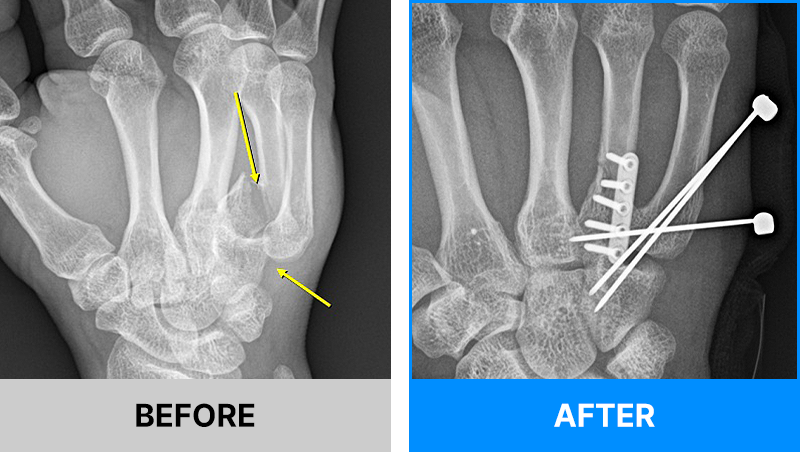

왜 당일 입퇴원 수술일까요?

오래 입원할 필요가 없기 때문입니다.

서울거탑정형외과에서는 전신마취, 척추마취가 아닌

국소부분마취(신경차단) 및 수면 마취를 통해 수술을 시행합니다.

수술 가능 여부 확인은 대표원장과의 진료가 필요합니다.